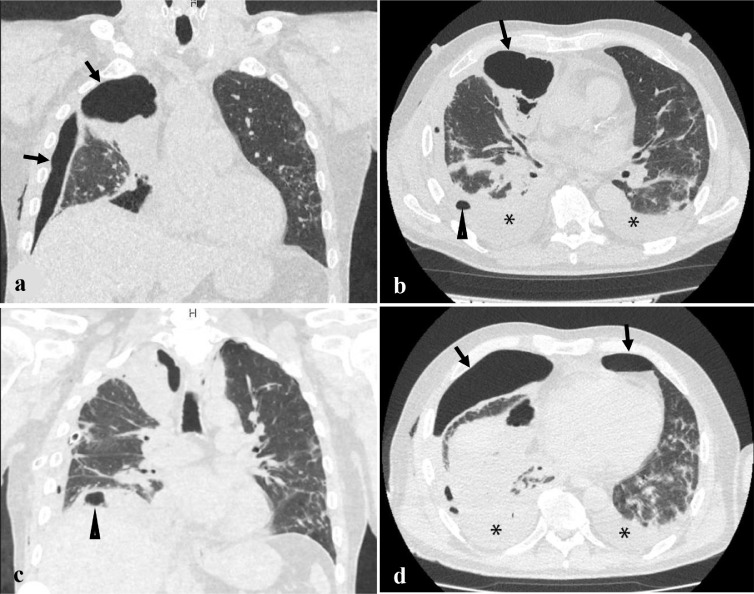

Daily drainage volume was from 300 to 1000 ml of fluid. Chest computed tomography obtained on day 3 after thoracentesis still showed pleural effusion with gas bubbles extended along the posterior and inferior walls of the right hemithorax (Fig. 3 a). The right lung was reduced in volume by half. In the S6 segment of the lower lobe, a focal area of subpleural infiltration with a central cavity of destruction up to 6.5 mm in diameter was revealed (Fig. 3 b,c). Air layer up to 47 mm of anteroposterior thickness was revealed along the anterior chest wall. Radiological sings of the left side hydropneumothorax were also found (Fig. 3 d). The pleural effusion with 25 mm of anteroposterior depth was revealed by the posterior surface of the partially collapsed lung. Air layer up to 19 mm of anteroposterior thickness was discovered along the anterior chest wall at the level of the lingular segments of the lung. In all lung fields multiple bilateral ground glass infiltrates were identified.

Fig. 3.

Air in the pleural cavity (arrow), pleural effusion (*) and focal area of infiltration with a central cavity of destruction (black triangular arrow) on coronal (A, C) and axial (B, D) reformatting images of chest CT on day 3 after thoracentesis (on the 18th day after admission)